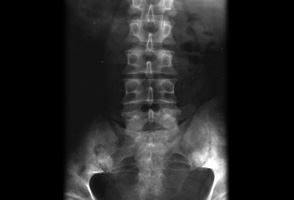

Plain radiograph showing bilateral sacroiliitis in a patient with ankylosing spondylitis

BMJ 2006;333;581-585. © BMJ Publishing Group Ltd 2009